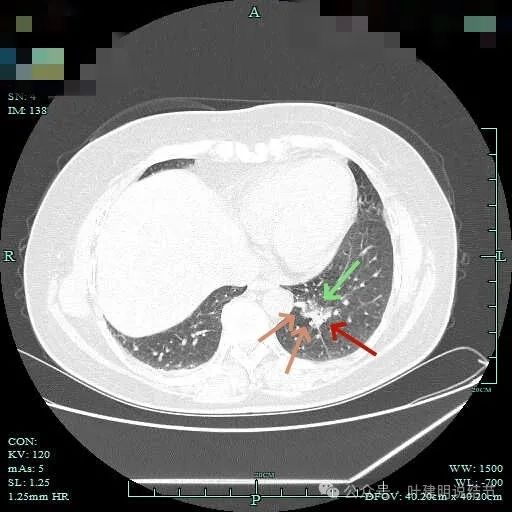

上图大部分是磨玻璃成分,边缘的毛刺征,表面有浅分叶。

上图层面已经基本上磨玻璃密度,轮廓清,灶内有囊腔样灶,表面不平。